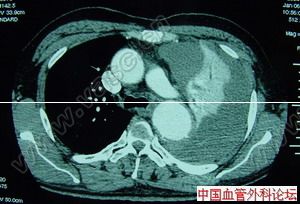

主動脈竇動脈瘤破裂主動脈竇動脈瘤是一種罕見的先天畸形,約占先天性心臟病患病率的2%~3.56%,其破入右室者最多,其次為右房。發生原因主要是胚胎期竇壁中層彈力纖維發育不良,在主動脈內高壓影響下,該薄弱處逐漸變薄擴張,呈囊袋狀突出,當壓力突然增加時破裂,由於主動脈和破入心腔間存在著較大的壓力階差,可產生大量的左向右分流,因而導致全心容量負荷增加,特別是外破口較大或破入右房者,病情進展快,容易發生充血性心力衰竭,部分患者易繼發心內膜炎、心律紊亂、腎功能衰竭等嚴重併發症。臨床多表現為起病急、進展快。一般認為,主動脈竇動脈瘤破裂之前多無明顯症狀和體徵,一旦破裂,即產生劇烈胸痛及顯著的血流動力學改變。破入右室、右房者可出現右心衰竭,呈進行性加重。體徵有胸骨左緣第3、4肋間連續性響亮機器樣雜音,常伴有肺動脈高壓、右心功能不全及脈壓差增大的表現。首次聽診往往有主動脈瓣受損的印象,易誤診為主動脈瓣關閉不全,本例即是此種情況。超聲心動圖是最佳的無創診斷法,可直接顯示主動脈竇動脈瘤的起源形態、突入的心腔位置、竇瘤破口大小、是否合併其他心臟畸形、分流的性質、時相、最大流速,提供血流動力學資料。一旦瘤體破裂,預後不良,可在數周至數月內因嚴重併發症死亡。內科治療只能起到短暫的減輕作用,手術治療往往可以獲得滿意的效果。該戰士因沒有及時手術,導致急性腎功能衰竭並時間過長,多臟器衰竭而死亡。